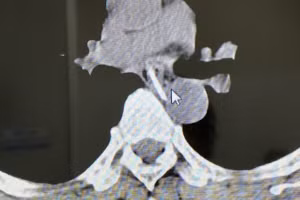

GD&TĐ - Bệnh viện Nhi Trung ương trong 3 ngày đã tiếp nhận 3 trẻ từ 17 - 21 tháng tuổi nhập viện trong tình trạng suy hô hấp vì bị hóc hạt lạc tại nhà.